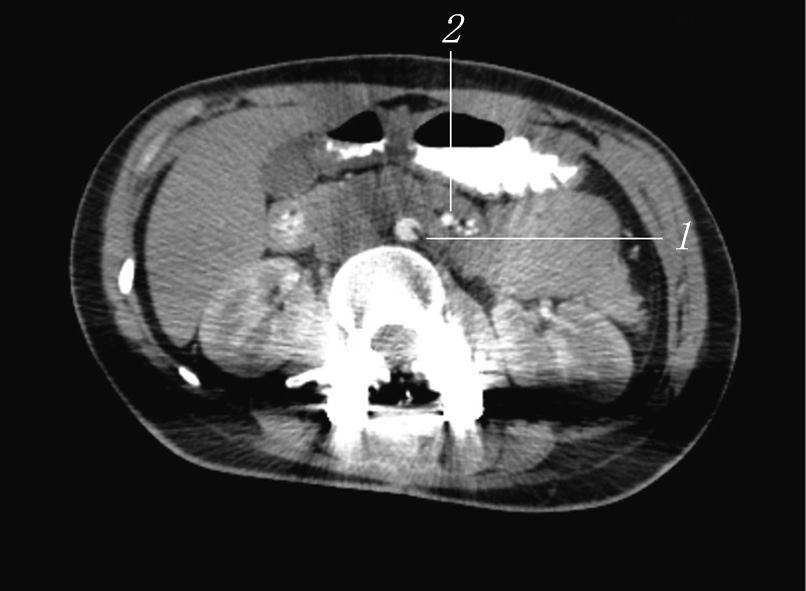

A combined MSCT with contrasting of the gastrointestinal tract and angiography of the abdominal cavity vessels was performed (Fig. 6). In specific, a tube was installed to the level of the duodenum, without distal disturbances in the contrast agent passage. Contrast agent traces in the small and large intestine were found. The stomach was not enlarged, the gas bubble was 110 × 40 mm, and the contents were traces of fluid. When contrasting of the vessels, the aortic–mesenteric angle was 7.7° (normal is 25°–60°), and the aortic–mesenteric distance was 5.1 mm (normal is 10–28 mm), which is a sign of SMA syndrome.

Fig. 6. Combined multispiral computed tomography with contrasting of the gastrointestinal tract and angiography of the vessels of the abdominal cavity: 1 — aorta; 2 — superior mesenteric artery

For 1.5 months, the patient received conservative therapy, during which complete assimilation of food introduced through the mouth and independent emptying of the intestine were achieved. On the control CT angiography, the aortic–mesenteric angle was 17° (norm 25°–60°), and the aortic–mesenteric distance was 13 mm (norm 10–28 mm) (Fig. 7). However, the patient continued to eat in small portions and experienced discomfort and nausea after eating a large amount of food. To select further treatment approach, monitoring by an abdominal surgeon was recommended to the patient.

Fig. 7. Control computed tomography: 1 — aorta; 2 — superior mesenteric artery